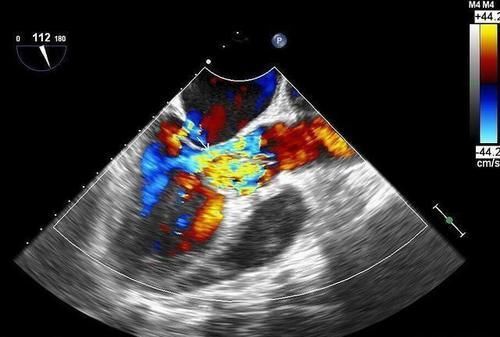

问的人多了,看来还是很多人想了解心脏彩超,那我们就来了解一下心脏彩超能看到些什么,能诊断什么病,一些常见的我们来看一看。(1)先天性心脏病:先天性心脏病指的是在胎儿期,心脏大血管发育异常,导致心脏存在畸形,与正常人不一样。一生出来就存在,娘胎里带来的。通过心脏彩超检查,可以诊断几乎所有类型先天性心脏病,当然这对检查的医生的技术要求很高,尤其是一些复杂畸形。比如下图这个,就是一个常见的先天性心脏病,叫做动脉导管未闭。

(2)心脏瓣膜疾病:人体心脏内有4组心脏瓣膜分别是二尖瓣,三尖瓣,主动脉瓣,肺动脉瓣。通过心脏彩超检查可以发现瓣膜是否有狭窄或者关闭不全等。下图就是一个二尖瓣关闭不全的报告。